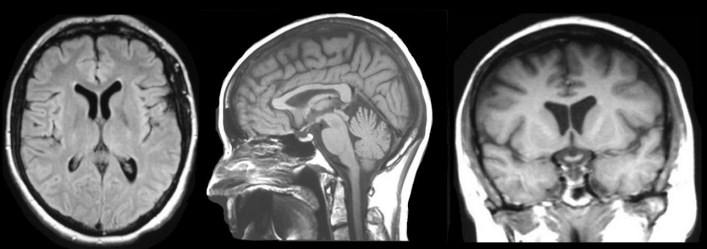

Axial

Sagittal

Coronal

Voxel size for CT: 0.625-1.25 mm^3

similar to MRI